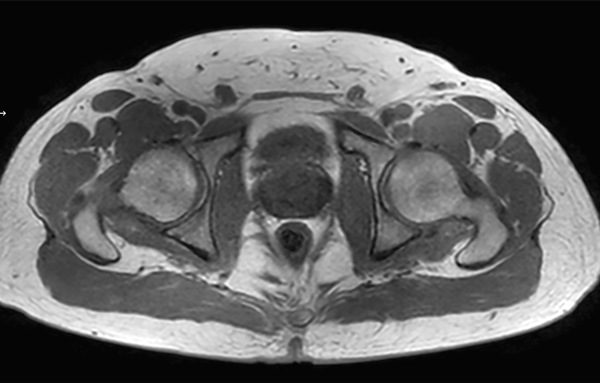

Motion-free Prostate imaging